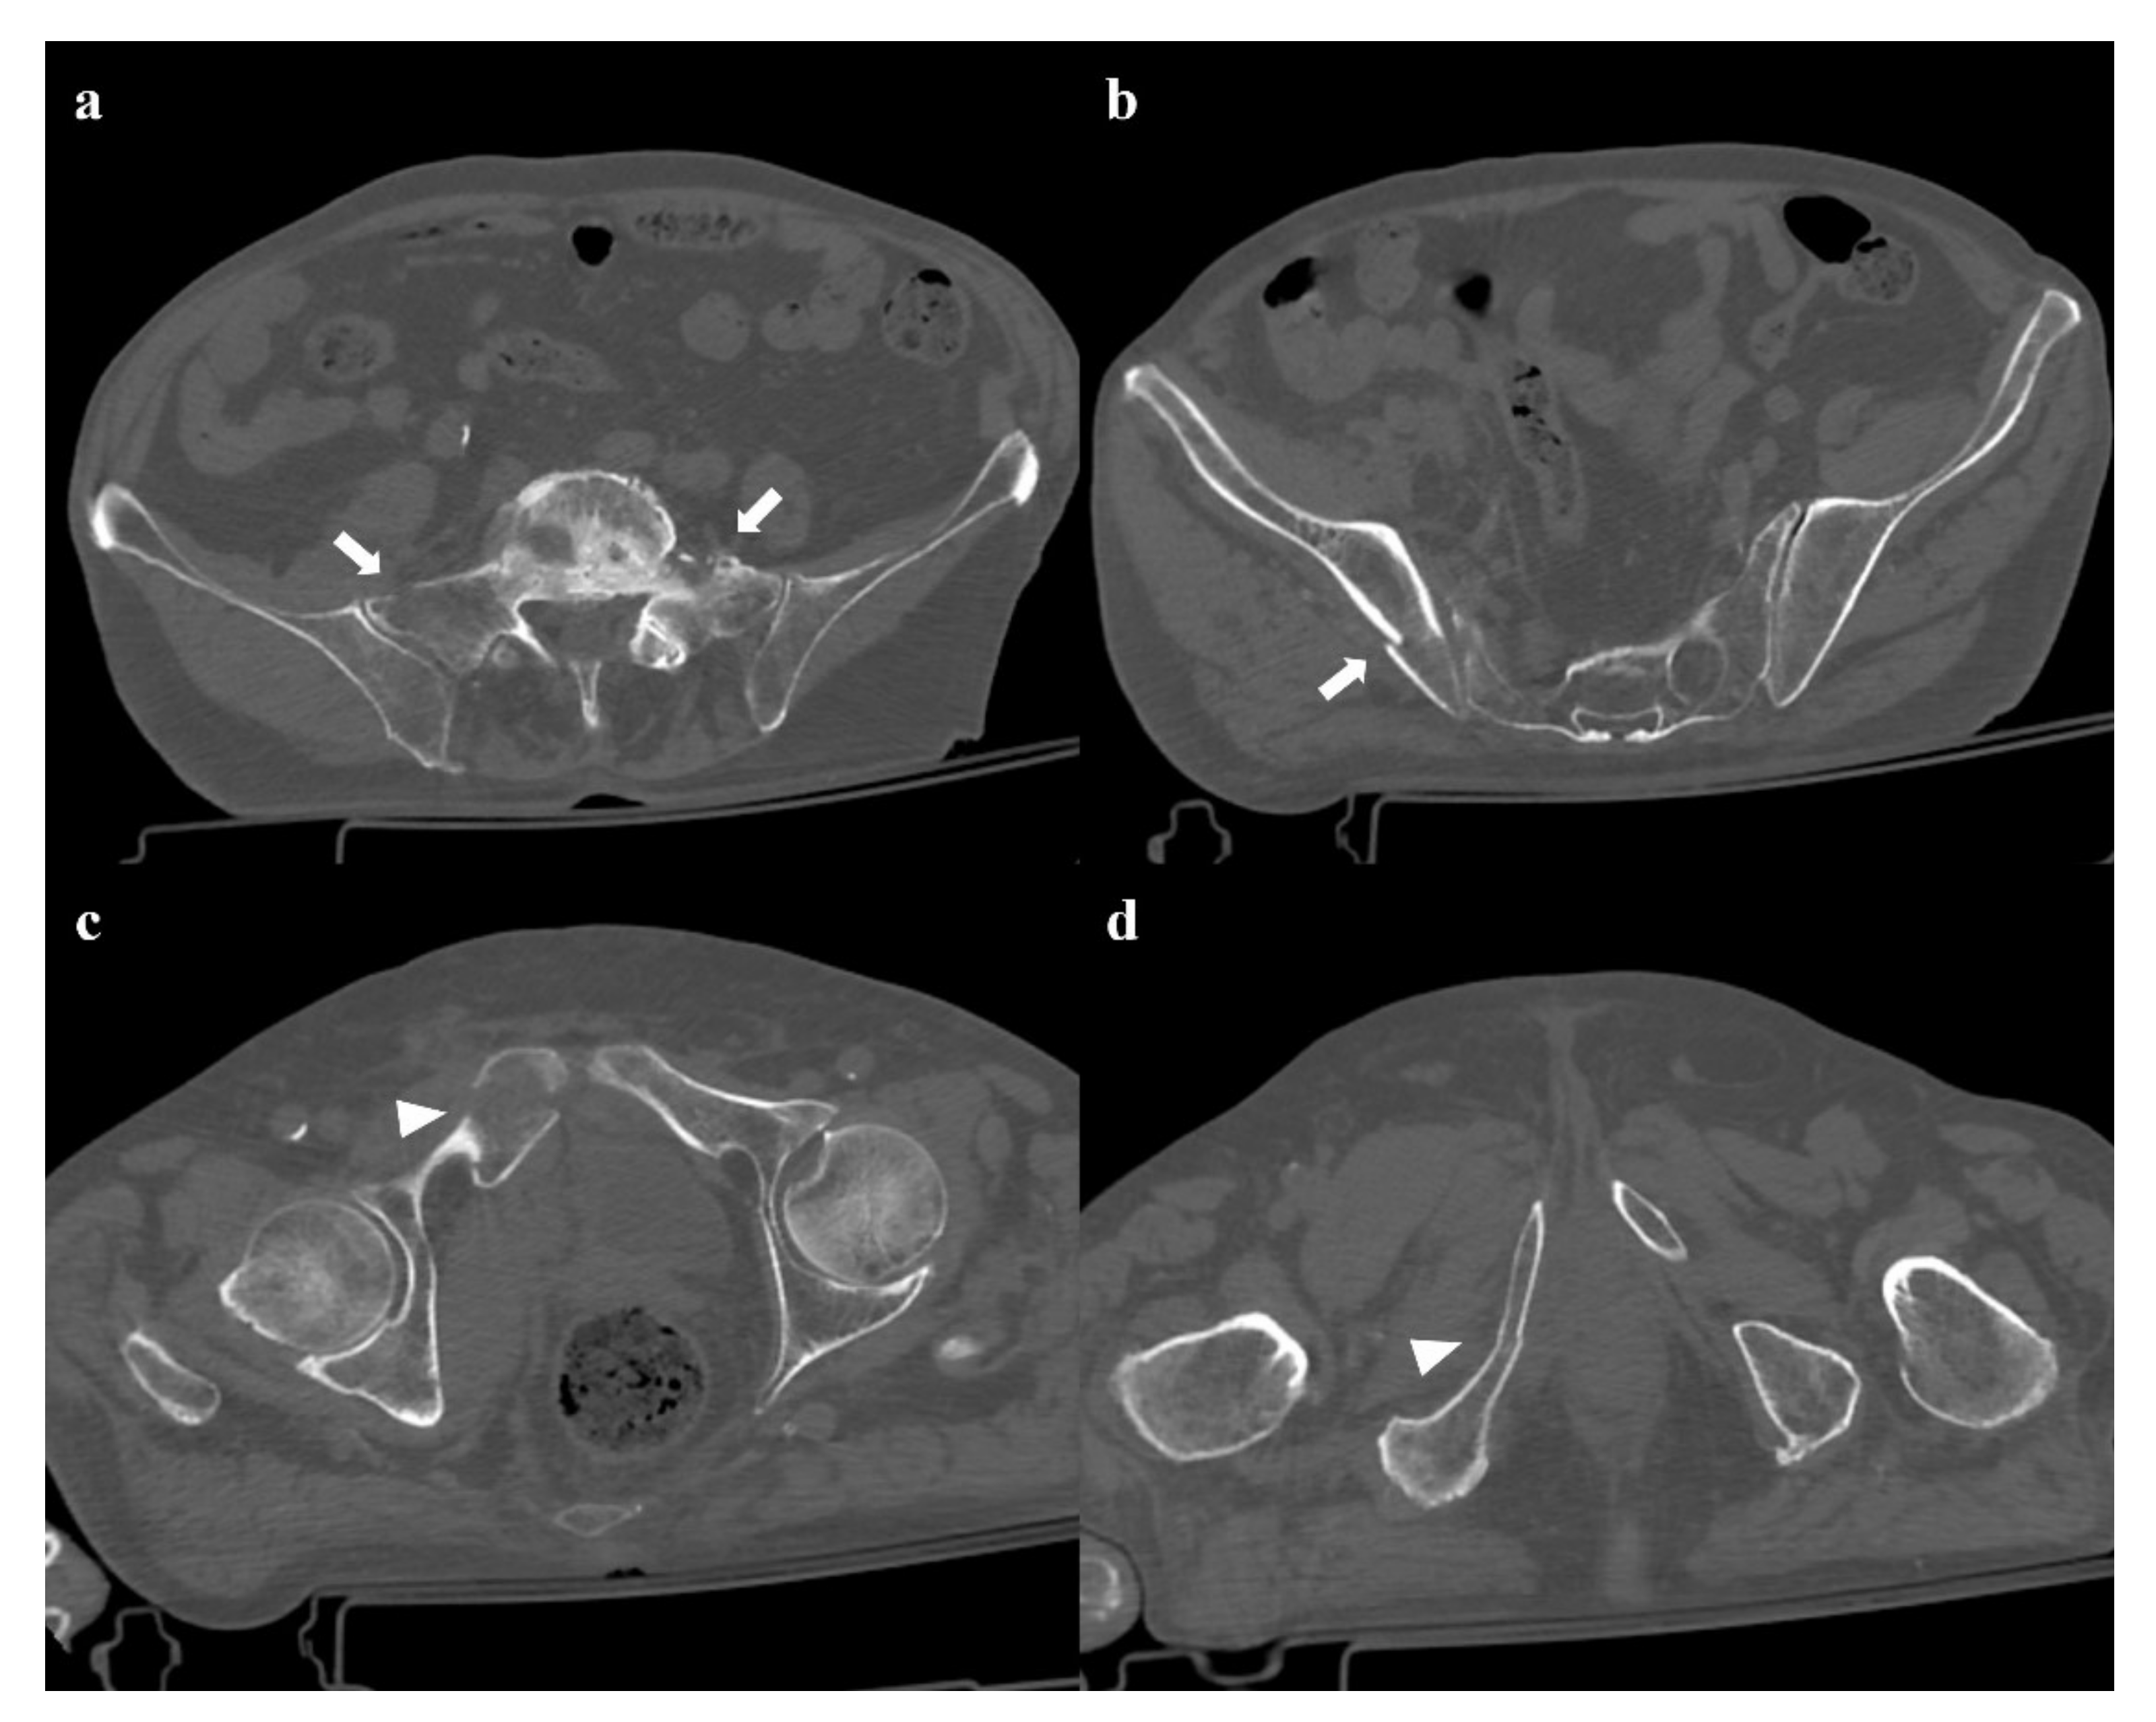

- Zone I: the fracture is located in the sacral wing, lateral to the neuroforamina (Figure 2). In 6% of cases, there is an impingement of L5 or S1 nerve root.

- Zone II: the fracture involves the neuroforamina (Figure 1). In 28% of cases, there is an ipsilateral neurological deficit.

- Zone III: the fracture is medial to the neuroforamina and involves the central canal. A combined fracture in this zone may have different morphology (“H”-shaped, “U”-shaped, “λ”-shaped, “T”-shaped), and can result in a spinopelvic dissociation (Figure 8). Zone III fractures can also be divided into four additional groups: anterior angulation of the fracture without dislocation (type 1), anterior angulation of the fracture with retrolisthesis (type 2), complete anterolisthesis of the fracture fragments (type 3), and comminuted fracture of S1 or S2 (type 4) [22]. In zone III fractures, there is a neurological injury in 56% of cases, with bowel and genitourinary dysfunction [8].